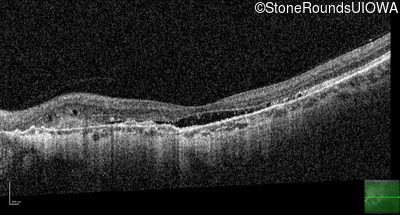

Age at visit: 58 years